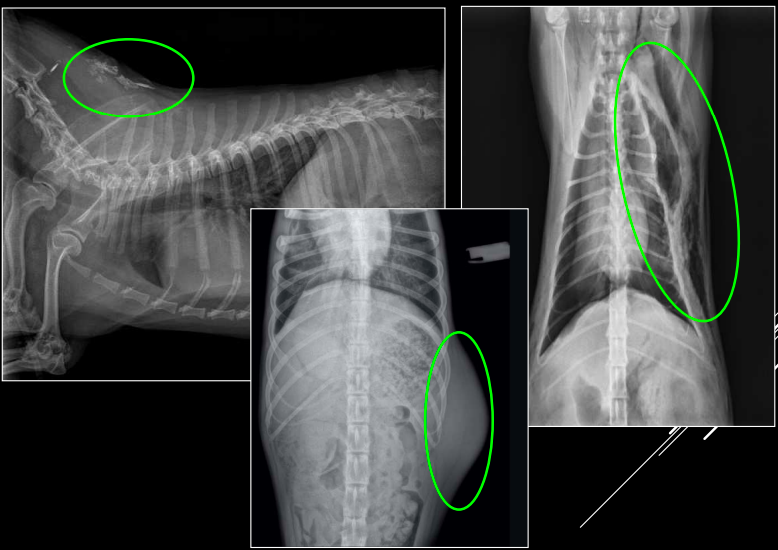

- Alteraciones de posición del mediastino (Desplazamiento mediastino VD)

- Alteraciones en la visualización de estructuras mediastinicas (Neumomediastino LL)

- Alteraciones de la anchura del mediastino (Derrame mediastinico o masa mediastinica VD)

1. Desplazamientos

- Artefacto (rotación): desplazamiento no real. Si se ve el esternon está mal

- Por enfermedad pleural (neumotórax): desplazamiento no real.

- Masa mediastínica: desplazamiento real.

2. Neumomediastino

- Aire en mediastino craneoventral.

- Mayor visualización de estructuras mediastínicas en vez de ver efecto masa en la zona mediastinica craneal, presencia de negros en la zona craneal y mejor visualización de vasos y traquea.

- Enfisemas subcutaneos suelen ocurrir, quedando aire entre las fascias y subcutaneo. Incluso puede pasar a la cavidad abdominal.

- “Tracheal stripe sign”.

- Puede coexistir con enfisema subcutáneo, neumotórax o neumoretroperitoneo.

- Generalmente por rotura traqueal (A veces por rotura esofágica)